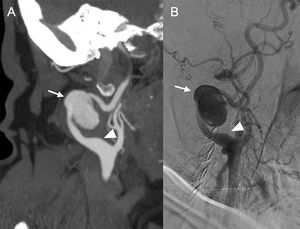

Most pseudoaneurysms that form in the carotid territory are of undetermined origin. Pseudoaneurysms in the common carotid artery are rare; they account for 0.3–14% of all aneurysmal disease and 0.5–1% of all surgical interventions on the carotid. Most cases are diagnosed incidentally and they may occur due to rupture of an atheromatous plaque with intimal tear. A high incidence of arterial hypertension, diabetes, COPD and coronary disease has been reported in these patients23 (Fig. 14).

66-year-old female smoker with a history of arterial hypertension, dyslipidaemia, pulmonary embolism and deep vein thrombosis who, for months has been able to palpate a pulsatile right laterocervical mass, with no apparent cause. An ultrasound scan was performed at her health centre, detecting an aneurysmal dilation of the right internal carotid artery. Sagittal maximum intensity projection reconstruction of supra-aortic trunk CT angiography in arterial phase (A) confirming the presence of the right internal carotid artery-dependent pseudoaneurysm (arrow), and arteriogram (B) used for endovascular treatment with stenting. Both images show vascular loops and segmental dilatations (arrowhead) involving bilateral vertebral and carotid territories, which in this patient had not been attributed to any disorder until now.